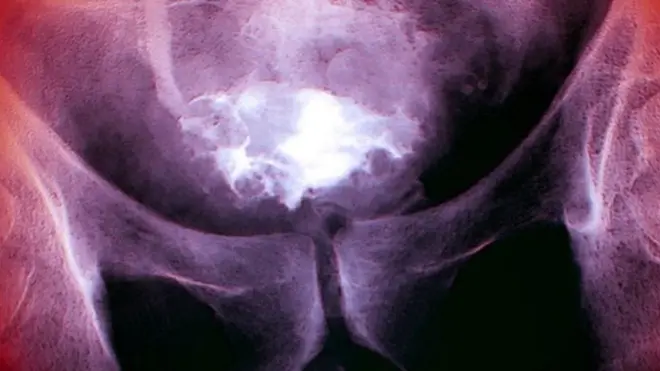

علاج الخصوبة عند الرجال قد يؤدي إلى سرطان البروستات

بينت دراسة علمية أن الرجال الذين يخضعون لعلاج الخصوبة معرضون أكثر من غيرهم لخطر الإصابة بالسرطان في مرحلة لاحقة من حياتهم.

وشملت الدراسة التي نشرت في "المجلة الطبية البريطانية" 1.2 مليون حالة ولادة في السويد، على مدار عشرين عاما. وكشفت أن الرجال الذين خضعوا "للحقن المجهري"، وهو علاج خصوبة خاص بالرجال، معرضون أكثر من غيرهم للإصابة بالسرطان.